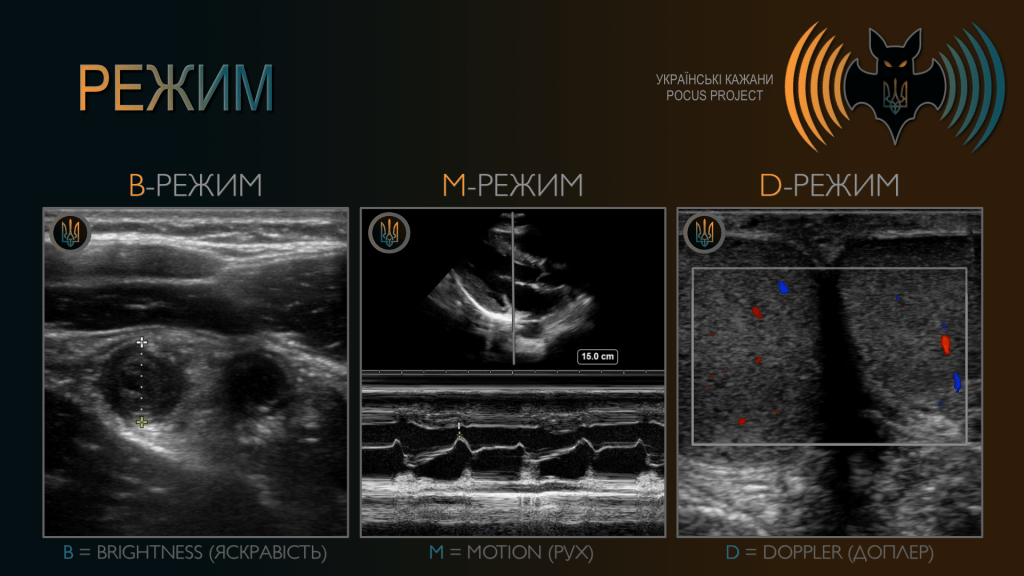

- B-режим (B-mode) — більшість обстежень виконується саме в B-режимі (brightness mode). У B-режимі відображається фактичний ультразвуковий вигляд даної структури.

- M-режим (M-mode) — використовується для оцінки руху тканин у часі. Застосовується, наприклад, для аналізу руху клапанів серця, стінок серця або ковзання плеври.

- D-режим (Doppler mode) — об’єднує різні модальності, що використовують ефект Доплера для характеристики кровотоку. Найбільш базове його застосування — визначення наявності або відсутності кровотоку.